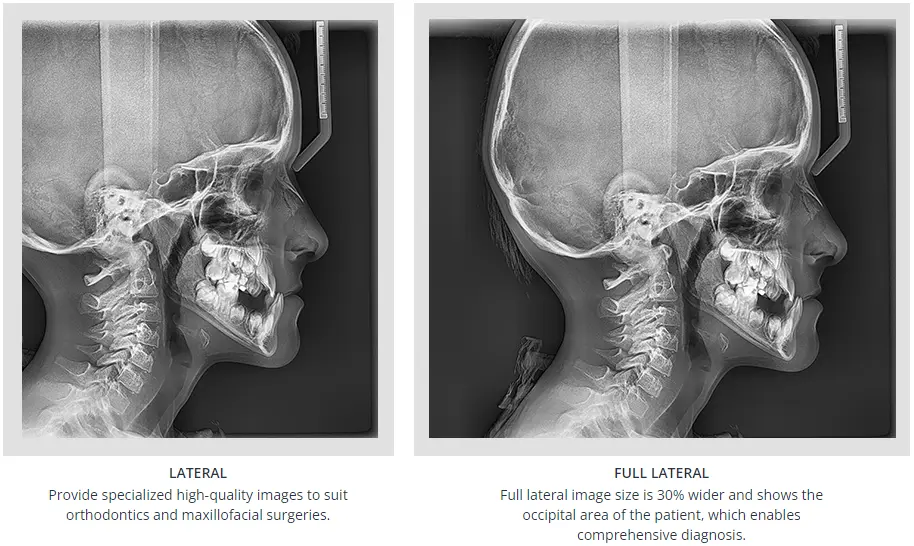

This facory certified Vatech PaX-i SC pan ceph X-ray machine provides consistently clear and detailed panoramic and cephalometric X-ray images, enhancing diagnostic precision and fostering greater treatment acceptance. With dedicated, built-in sensors for both panoramic and cephalometric imaging, this machine ensures exceptional digital imaging quality, while also boosting practice efficiency.

Optimal image for accurate diagnosis - Two Dedicated Sensors